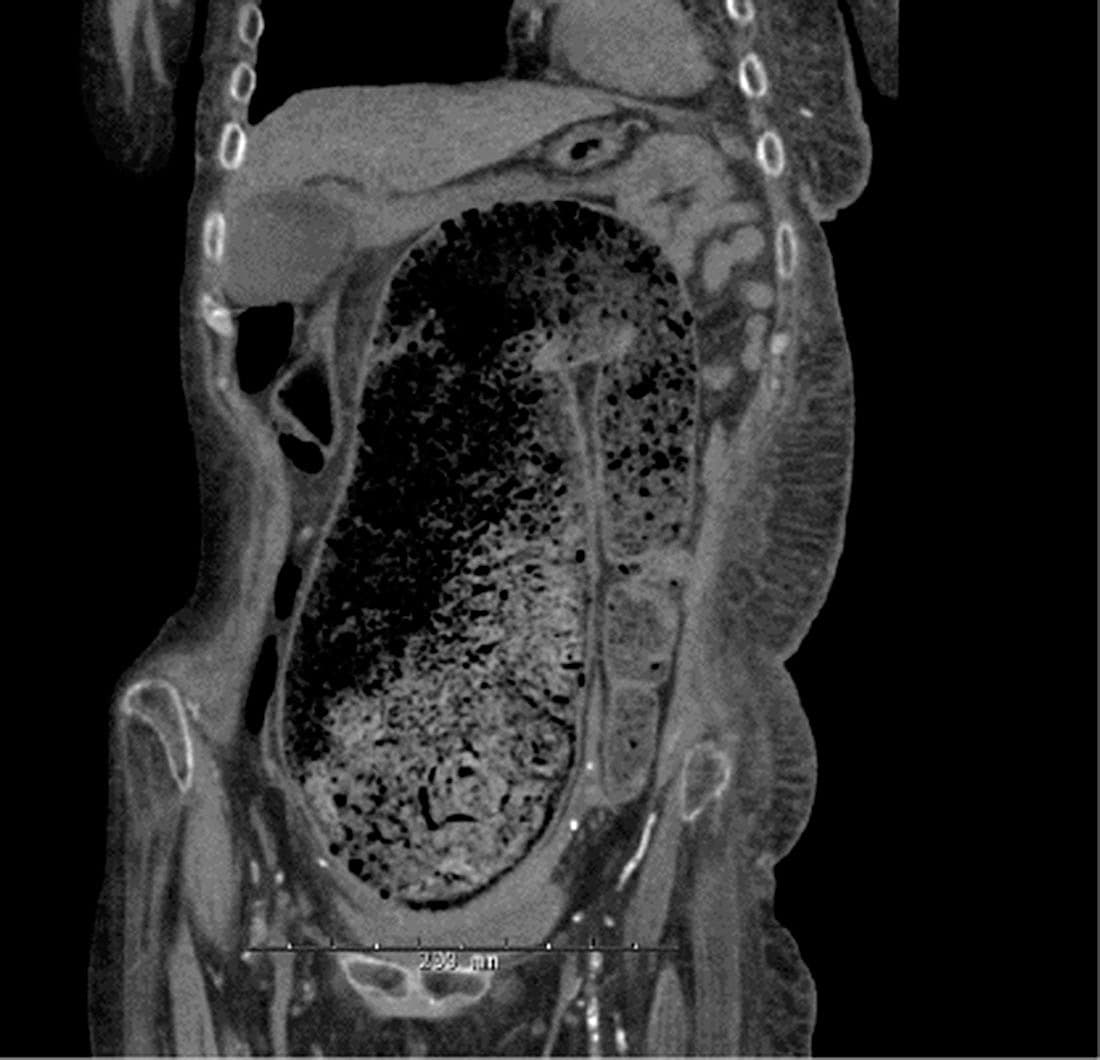

En 55-årig kvinde, der var i kronisk hæmodialyse, blev indlagt med svær obstipation gennem otte dage. En røntgenoversigt over abdomen viste, at sigmoideum elongatum var udtamponeret af fæces. Hun havde ikke tegn på ileus, og man påbegyndte konservativ behandling med klysma på rektalsonde og laksantia via ventrikelsonde. Pga. tiltagende mavesmerter og blødning per rectum blev der foretaget en CT af abdomen, hvor der sås mønstrøs koprostase i sigmoideum og rectum. Tarmlumen blev målt til 12 cm i diameter. En koloskopi viste mulig blødning, men ingen tegn på obstruerende tumor. Patienten fik fortsat konservativ behandling.